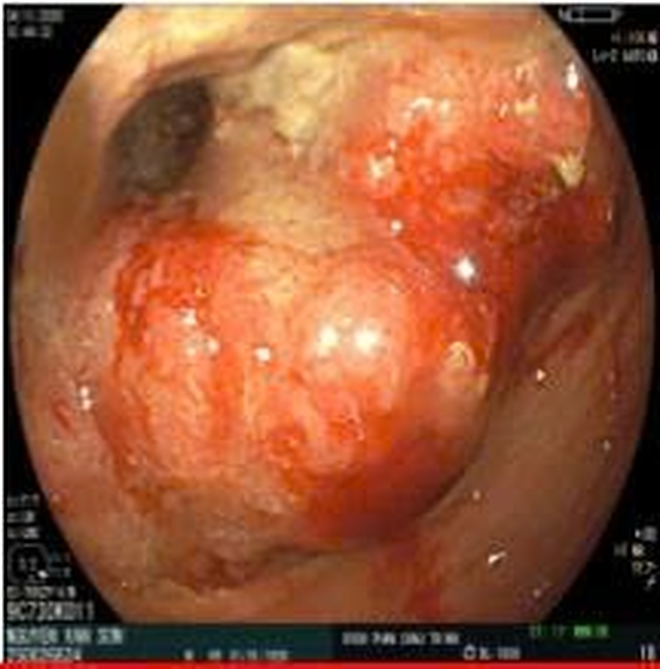

Tuy nhiên, dựa trên bệnh sử kéo dài và yếu tố nguy cơ tuổi cao, bác sĩ chỉ định nội soi đại–trực tràng bằng hệ thống nội soi mới nhất của Fujifilm tích hợp trí tuệ nhân tạo (AI). Hình ảnh nội soi cho thấy tổn thương u sùi chiếm toàn bộ chu vi trực tràng, cách rìa hậu môn 15 cm, dễ chảy máu.

Công nghệ AI tích hợp trên hệ thống nội soi hỗ trợ phân tích hình ảnh theo thời gian thực, khoanh vùng nghi ngờ ác tính và giúp bác sĩ đánh giá bề mặt tổn thương rõ ràng hơn. Việc ứng dụng AI giúp giảm nguy cơ bỏ sót các tổn thương dù là nhỏ nhất và tăng độ chính xác trong chẩn đoán ngay từ thủ thuật đầu tiên